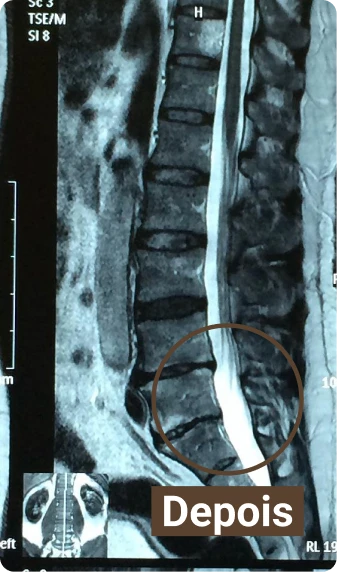

Veja por exemplo esse caso, paciente estava com uma hérnia de disco grande, ficou preocupado quando recebeu o diagnóstico do exame, já era indicação cirúrgica, mas em poucas sessões conseguimos reverter, somente com o tratamento conservador.

O tratamento foi sem necessidade de cirurgia